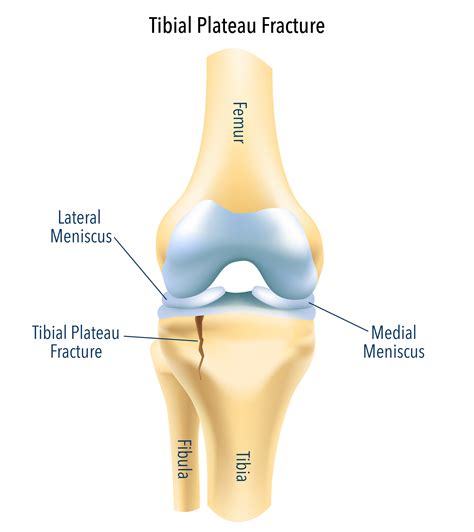

The knee is a complex joint where the femur (thigh bone) meets the tibia (shinbone). The tibial plateau is the flat, top surface of the tibia, covered in cartilage to ensure smooth movement. When excessive force is applied to this area, the bone can crack or shatter. This type of injury often results from high-energy trauma, such as car accidents or falls from significant heights, though it can also occur in older individuals with lower bone density due to minor accidents.

Because the tibial plateau is integral to stability, a fracture here is considered a serious injury. It not only damages the bone structure but can also affect the soft tissues, ligaments, and nerves surrounding the knee joint. Proper diagnosis using imaging techniques like X-rays or CT scans is critical to determine the severity and the best course of treatment.